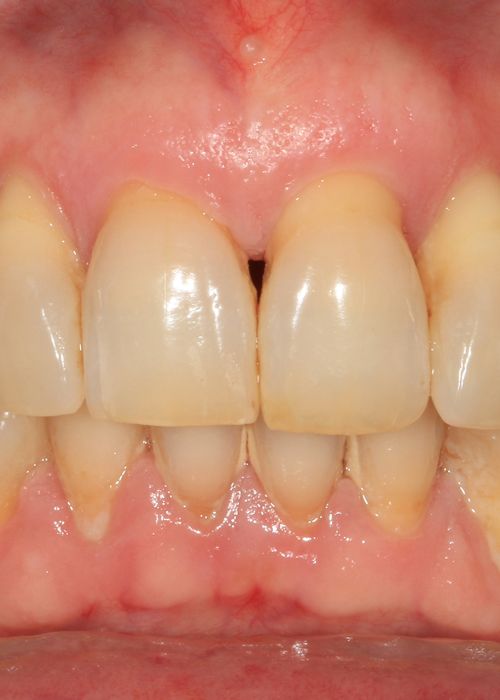

Resolución de un caso con implicación estética en el sector antero-superior. A propósito de un caso